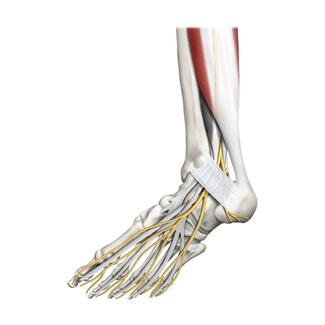

Can Tarsal Tunnel Decompression Treat Digital Contractures?

A case study poster presented at the American College of Foot and Ankle Surgeons Scientific Conference showed tarsal tunnel decompression led to improvement in clinical signs and intrinsic muscular balance.